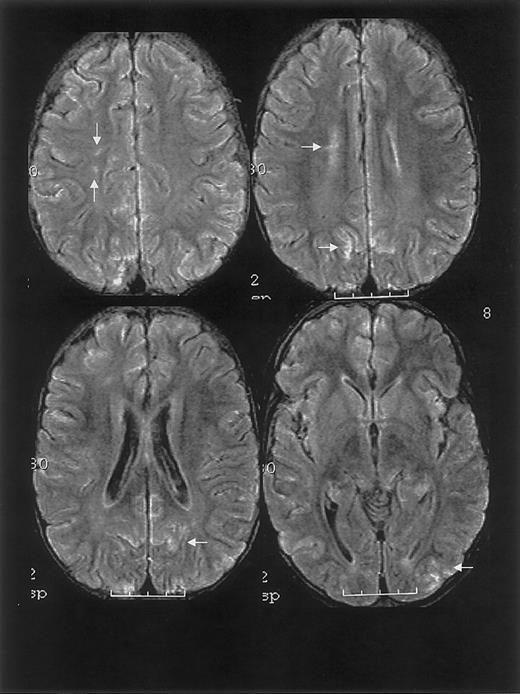

One year prior to ACS episode, the patient had normal MRI/MRA and transcranial Doppler studies. MRI on day 10 and 1 month following discharge revealed RPLS with superimposed ischemic white matter changes (Figure 2).

MRI findings for case 2.

Multifocal areas of signal hyperintensity predominantly limited to the cortex of the posterior parietal and occipital lobes on FLAIR T2-weighted images, including punctate areas of abnormality in the deep, periventricular white matter of the right frontal lobe and of the cortex of the right medial parietal lobe. MRI done 1 month following discharge revealed punctate lesions in the frontal lobe, representing subacute to chronic ischemic changes, but resolution of the T2 hyperintense lesions in the posterior distribution.